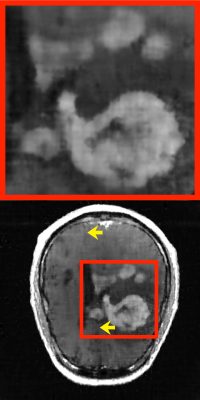

Refer to caption

Figure 3: Qualitative and quantitative results for acceleration factor analysis. The top figure shows reconstruction results for IFFT and the proposed method when R=4,8,12𝑅4812R=4,8,12italic_R = 4 , 8 , 12. Three graphs below present SSIM, PSNR, and training time results.

III-C Acceleration factor analysis

This subsection examines the effectiveness of the number of spokes to the reconstruction accuracy of the proposed method. Qualitative and quantitative evaluation results are provided in Fig. 3. In this experiment, the golden-angle sampling (46) was used.

We observed reconstruction results by gradually increasing R𝑅Ritalic_R from 2 to 12. As R𝑅Ritalic_R is increased (i.e., Nφsubscript𝑁𝜑N_{\varphi}italic_N start_POSTSUBSCRIPT italic_φ end_POSTSUBSCRIPT is decreased), the reconstruction ability becomes, of course, weakened. However, the results were constantly superior than those from IFFT in both qualitative and quantitative perspectives. Notably, even for a high acceleration factor of R=12𝑅12R=12italic_R = 12 (41 spokes), the proposed method provided a high-quality MR image. Meanwhile, R𝑅Ritalic_R is associated with the training time of MLPϑsuperscriptMLPbold-italic-ϑ\text{MLP}^{\boldsymbol{\vartheta}}MLP start_POSTSUPERSCRIPT bold_italic_ϑ end_POSTSUPERSCRIPT in (21), since acquired samples are inputted for training. In other words, the larger R𝑅Ritalic_R, the shorter the training time, as shown in the bottom graph of Fig. 3. Note that the inference time is independent to R𝑅Ritalic_R, only affected by the image resolution to be reconstructed. In our case, the inference time was 0.61 seconds approximately for any R𝑅Ritalic_R.

When taking account of the compromise among the reconstruction quality, training time, and scan acceleration, R=8𝑅8R=8italic_R = 8 (62 spokes) may be regarded as an empirically optimal choice.